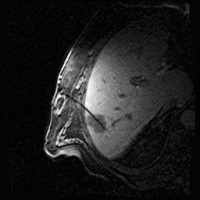

Under local anesthesia and administration of pain medication, the tumor is punctured under computer tomographic (CT), magnetic resonance imaging view with subsequent insertion of the catheters into the target volume.

Images: Brachytherapy for liver metastases: first MRI-guided placement of one catheter per tumor followed by irradiation through the catheters using Iridium 192 radiation source.